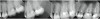

Figure 8  Preoperative and postoperative radiographs of the upper left quadrant, where endodontic therapy was performed in a single visit pre-prosthetically. With two 4-canal molars and a 3-canal premolar, a total of 11 canals were treated in a 2.5-hour appointment as a result of effective use of current technology.

Figure 8

As a result of recent technological advances and a thorough understanding of the canal anatomy, improved instrumentation and obturation techniques have dramatically improved the efficiency of the endodontic procedures dentists perform. When required, multiple endodontic cases can be performed today in one sitting with minimal trauma to the patient while achieving optimal results (Figure 8).